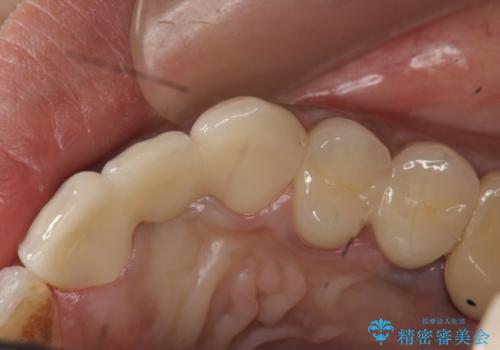

左上2番目の歯は歯根が破折してため抜歯し、左上123のブリッジによる欠損補綴を行いました。

左上4、5番目の歯は根尖病変を認めたため再根管治療を行い、オールセラミッククラウンによる補綴を行いました。

今回用いたオールセラミッククラウンは、ジルコニアフレームという白い素材の上にセラミックを盛っているため審美性が非常に高いのが特徴です。

またジルコニアは人工ダイヤモンドの材料にも使われているほど高い強度を持っており、そのためオールセラミッククラウンは審美性だけでなく、奥歯やブリッジの補綴も可能とするクラウンです。